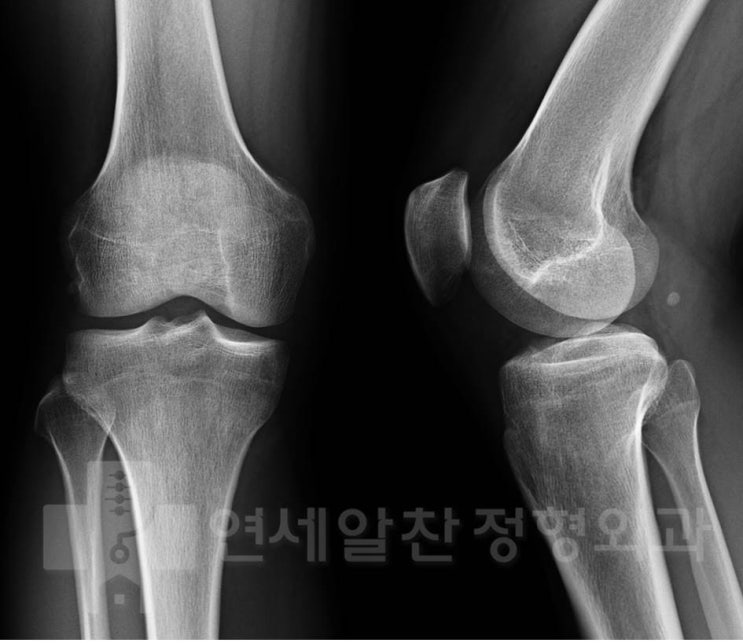

무릎 퇴행성 관절염에서 수술적 치료의 선택 (인공관절 vs 카티스템 vs 근위교정절골술)

71세 남자 환자분이 오랜기간 좌측 무릎통증으로 인해 여러병원을 다니시다 치료적인 결정을 하지 못해 무...